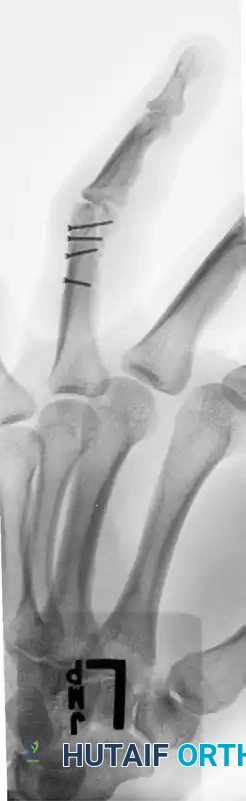

Case Example: Three-Part Displaced Intra-articular Fracture

Preoperative Evaluation:

The following radiographs demonstrate a complex, three-part displaced intra-articular fracture of the proximal phalanx in a 27-year-old man. The articular surface is significantly disrupted, necessitating open reduction.

FIGURE 67-41 A: Preoperative anteroposterior radiograph demonstrating the intra-articular split.

FIGURE 67-41 B: Preoperative oblique radiograph highlighting the displacement and articular step-off.

FIGURE 67-41 C: Preoperative lateral radiograph showing the volar subluxation tendency.

The screw heads must be countersunk or carefully selected to ensure a low profile. The following radiographs demonstrate successful anatomic reduction and fixation.

FIGURE 67-41 D: Postoperative AP radiograph showing anatomic restoration of the joint line.

FIGURE 67-41 E: Postoperative oblique radiograph confirming flush seating of the minifragment screws.

FIGURE 67-41 F: Postoperative lateral radiograph demonstrating restoration of the sagittal alignment. Note that the small screw heads do not interfere with collateral ligament function.